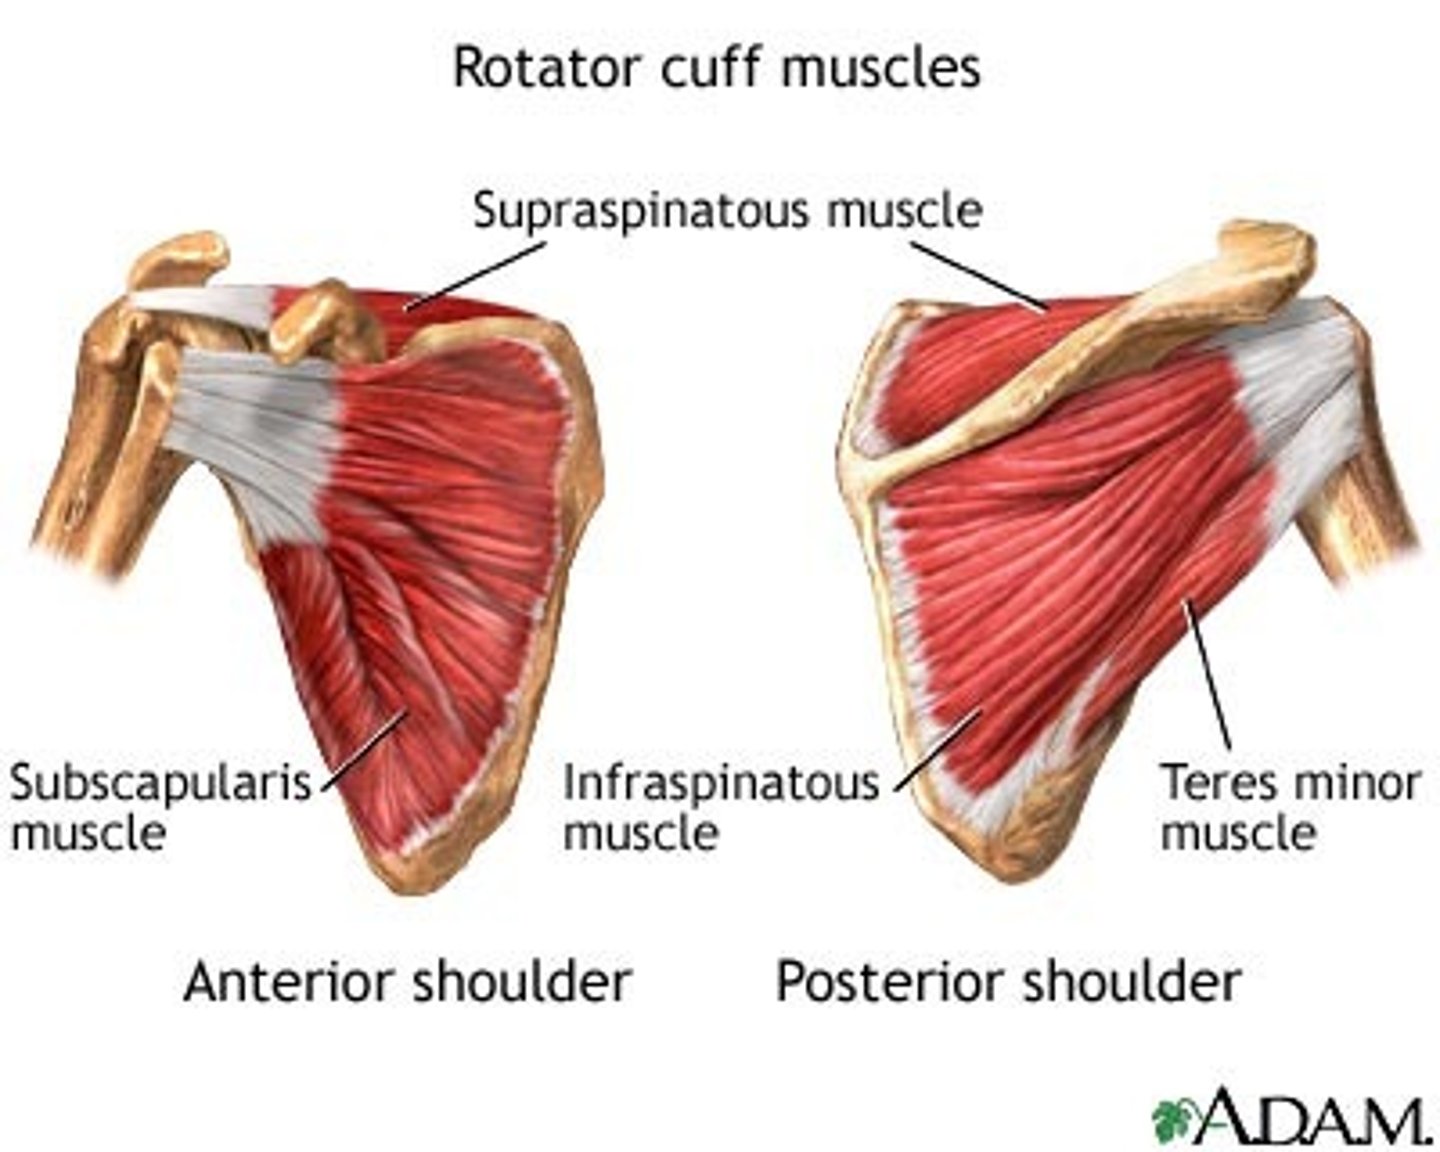

(Scapulohumeral muscles (intrinsic shoulder):) Rotator cuff muscles

Supraspinatus, Infraspinatus, Teres Major, Subscalpularis

(Rotator Cuff Muscles:) Supraspinatus

-Abduction of arm (assists deltoid in the initial 15˚)

-Suprascapular n. (C5 - C6)

(Rotator Cuff Muscles:) Infraspinatus

-Laterally rotates arm

-Suprascapular n. (C5 - C6)

(Rotator Cuff Muscles:) Subscapularis

-Medially rotates arm

-Upper and lower subscapular nerves (C5 - C7)